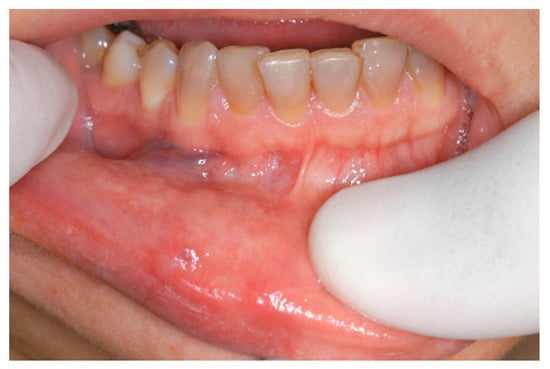

Aesthetic Treatment Outcomes of Capillary Hemangioma, Venous Lake, and Venous Malformation of the Lip Using Different Surgical Procedures and Laser Wavelengths (Nd:YAG, Er,Cr:YSGG, CO2, and Diode 980 nm)

2.2. Participants